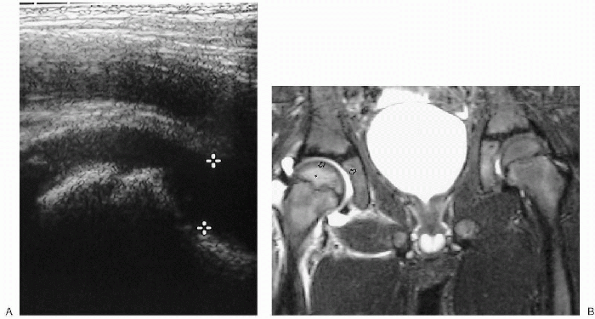

Figure 32-7 Hip effusion. (A)

Ultrasound. The capsule of the hip joint normally hugs the neck of the femur but when a joint effusion is present, the joint capsule is elevated away from the bone by the sonoluccent fluid (cursors). (B) Magnetic resonance T2-weighted imaging in another patient reveals a high signal-intensity fluid collection surrounding the right hip (arrows). Increased marrow signal (asterisk) is noted as well, consistent with edema. |

The most sensitive imaging modalities in the diagnosis of joint fluid is ultrasound or MRI (Fig. 32-7).

-

□ Ultrasound is the imaging modality of

choice in excluding a septic joint in that it offers the advantage of

speed and portability, as well as the ability for realtime-guided

needle aspiration of joint fluid. -

□ MRI may reveal an associated

osteomyelitis, if present, although similar information may be obtained

with bone scintigraphy following an initial ultrasound.